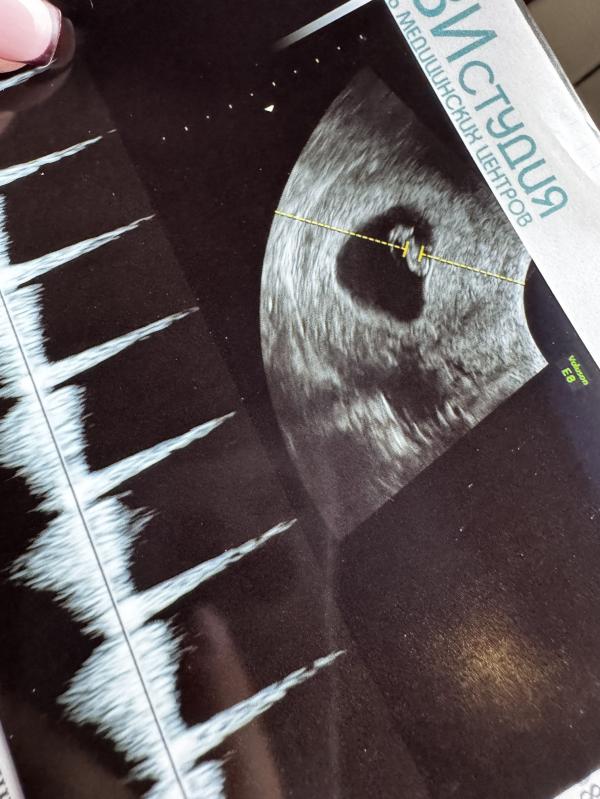

Была на узи, все отлично!

Срок соответствует 7-8 недель.

Прикрепление по передней стенки, предыдущие два раза были по задней 🙂